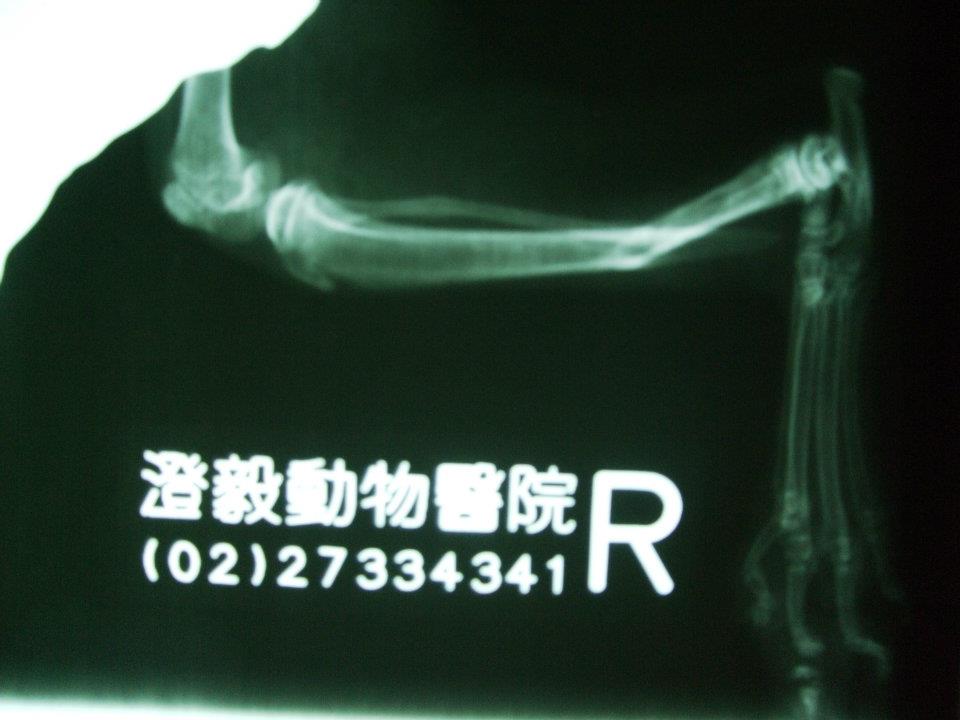

主題: 下顎、腿多處骨折的蜘蛛人 申請者姓名: 岳丹楓 花色: 申請日期: 2012-07-15 12:45:03 申請者部落格: 申請者臉書網址: 所在縣市/合作醫院: 台北市/澄毅動物醫院 治療費用: 4800元 需求人數: 12人 已結案 (2013-06-27 13:22:09) 報名人員: Bei Bei Wang(已付款)、Bei Bei Wang(已付款)、陳比比(已付款)、Ru Shiuan Liu(已付款)、SY Liou(已付款)、SY Liou(已付款)、牡羊先生(已付款)、Pomelo Peng(已付款)、Pomelo Peng(已付款)、orange liu(已付款)、Ku-ai Gina Chen(已付款)、艾薇拉、Kent、Athena Athena Tzeng、sally(已付款)、 候補人員: Patty Chen、julie lee、小P、 動物病情說明: 岳姊通報:陳小姐在龍門里捕捉or拾獲貓咪,嘴巴無法閉合行走姿勢怪異,送至醫院X光檢查發現腿部多處骨折、下顎骨折無法進食,插鼻胃管灌食,上點滴維持體力。